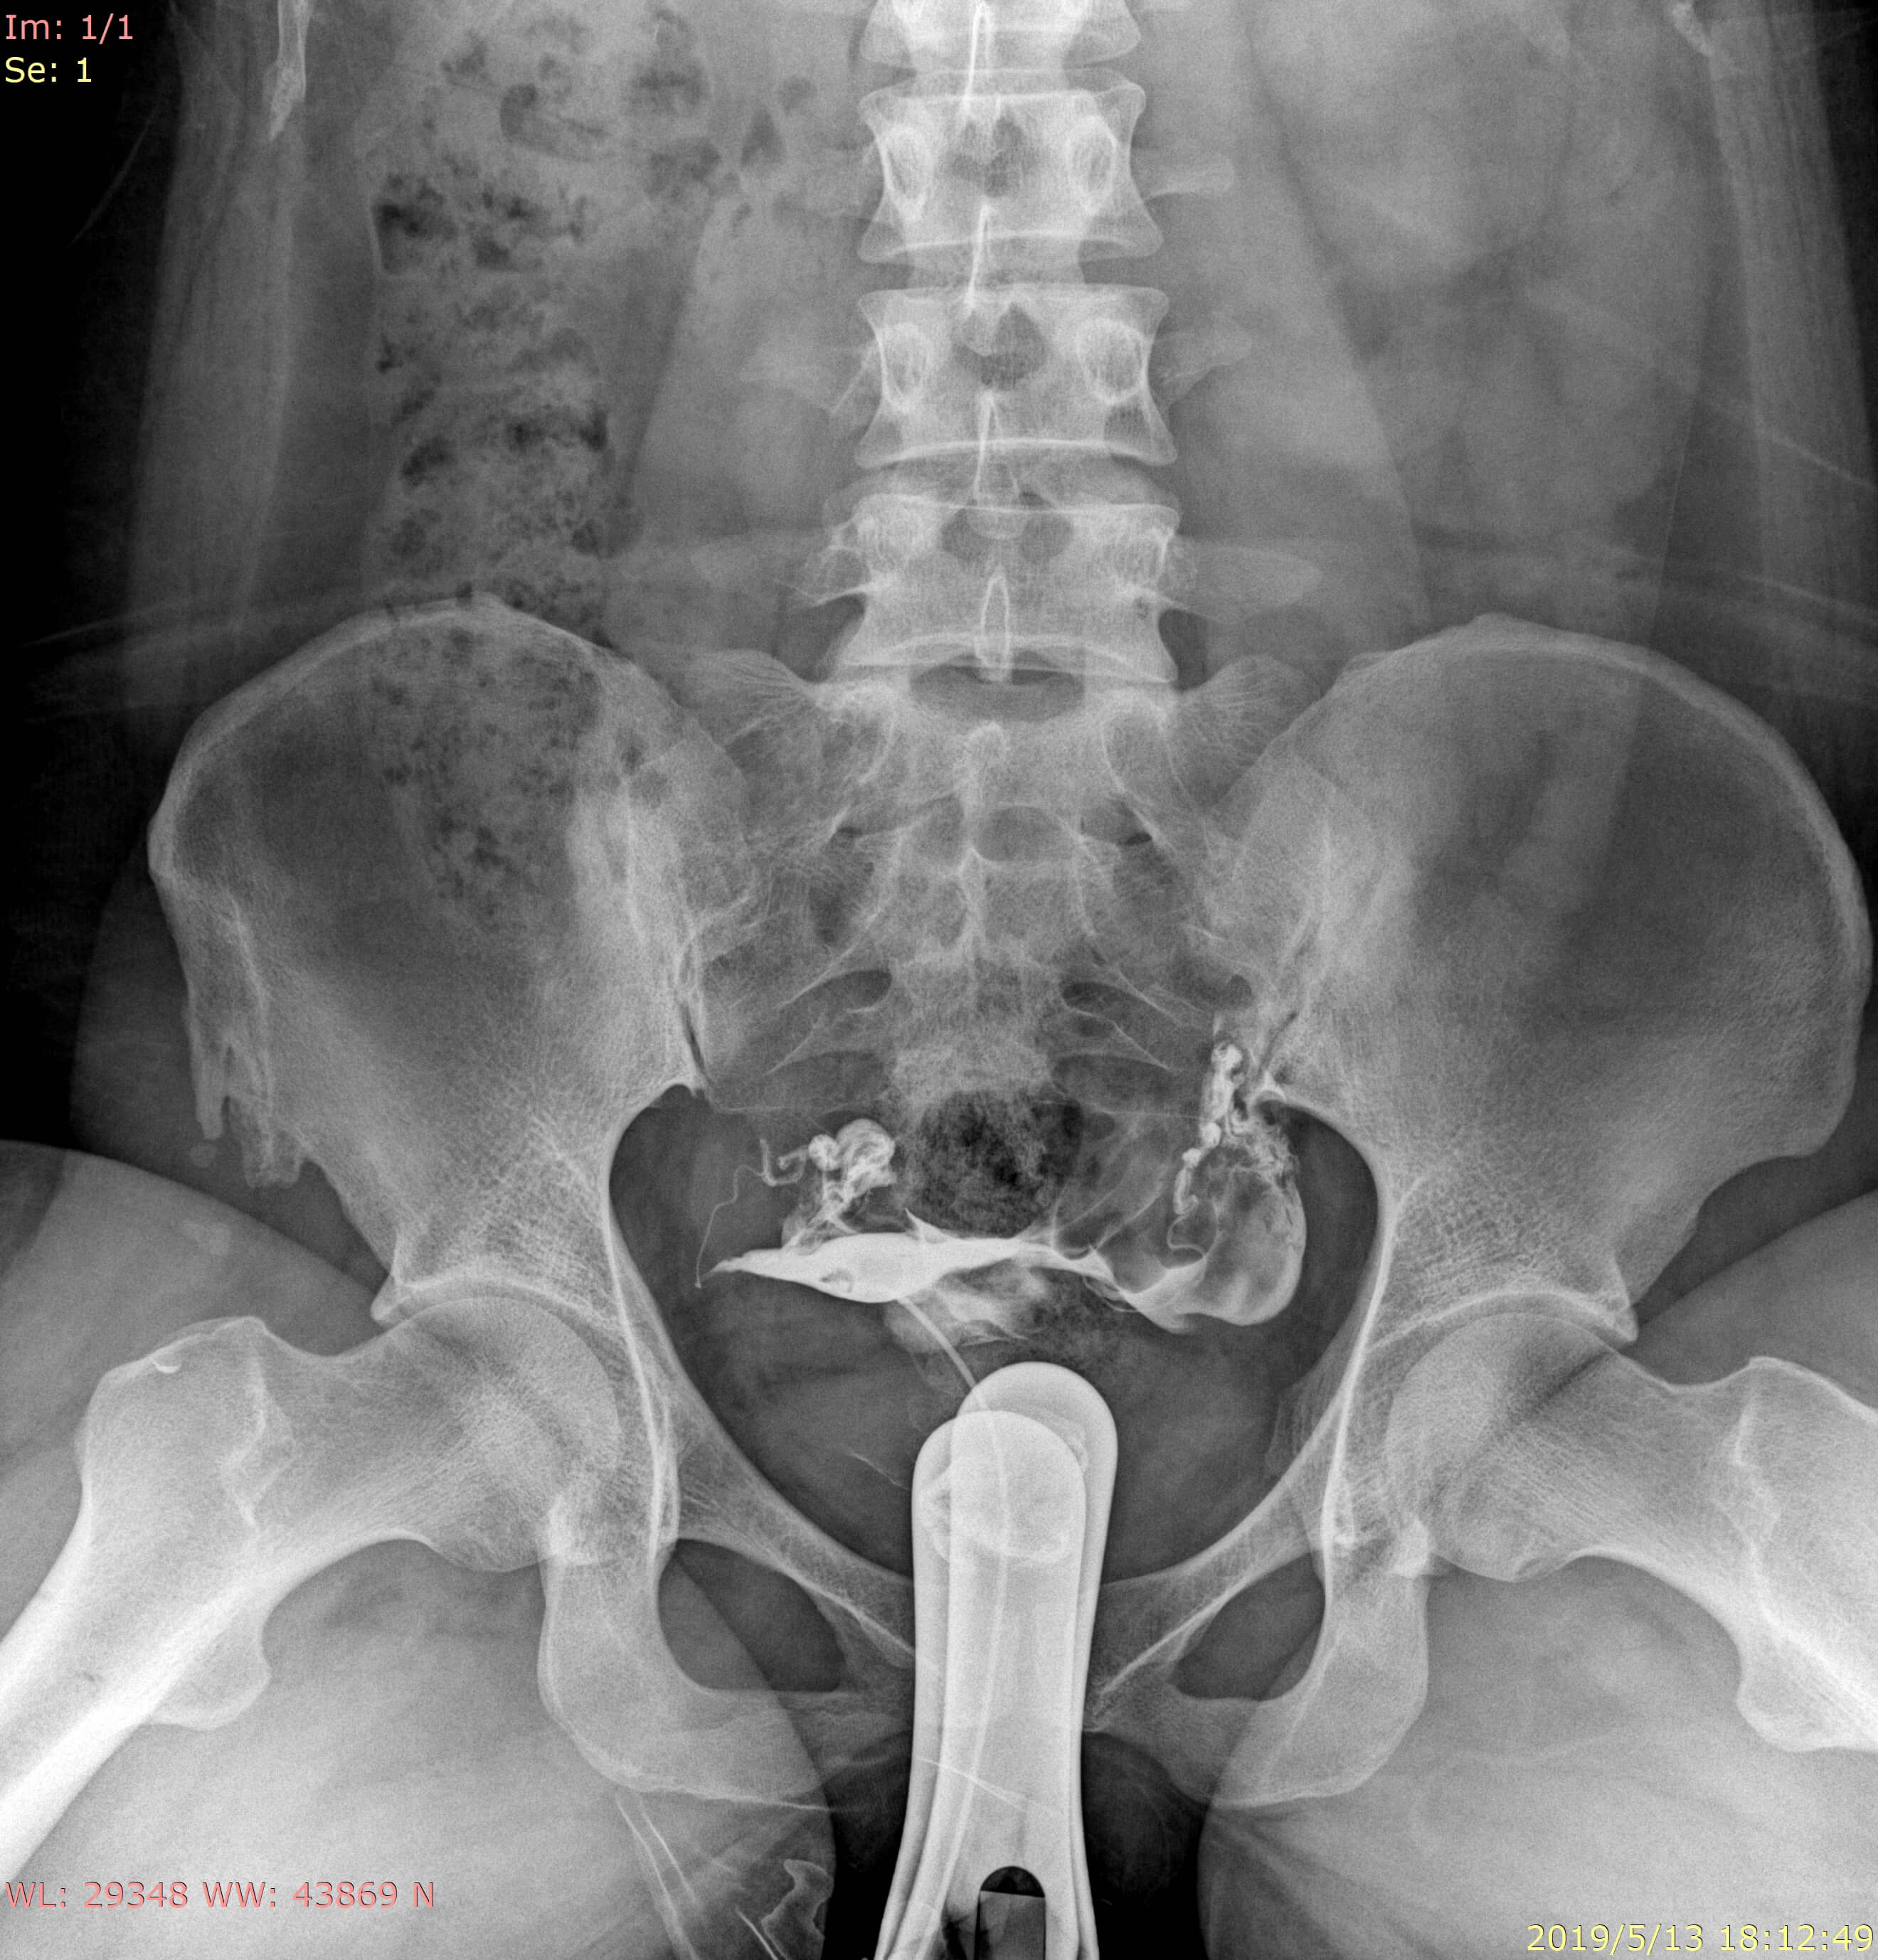

• Clinical Images